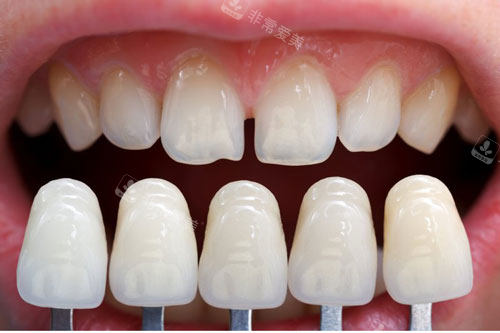

牙齿贴面颜色对比图

它引入了智能化的诊疗体系,比如智能口扫设备,能快速获取牙齿的3D模型,让矫正或种植方案更精密、可视。

在种植牙方面,他们熟练掌握像“All-on-4”这样的靠前技术。

这项技术通过巧妙的植入角度,能在骨量条件不理想的情况下,实现半口牙的快速修复,大大缩短了疗养时间,对时间紧迫的患者非常友好。